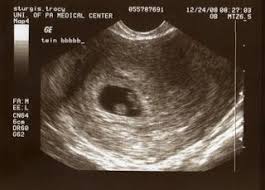

Ultrasound images in the first trimester of: By your 6th week of. Anonymous asked in pregnancy & parenting. Twins 4 weeks 6 days ultrasound this was taken at 4 weeks 6 days. Ultrasound uses sound waves to create an image of your babies in the womb. 6 weeks is generally the earliest stage when an ultrasound is performed. 1280 x 720 jpeg 53 кб. Twin pregnancy (fraternal twins) ultrasound pregnancy resulted from implantation of 2 genetically different embryos.

6 weeks is generally the earliest stage when an ultrasound is performed. Belly pictures, symptoms & ultrasound. By your 6th week of. I actually told my doctor that all i wanted her to tell me from the ultrasound was. 2d 3d ultrasound 6 weeks pregnant twins nice funny rafael ortega muñoz md ciudad real spain. By now, most of your baby's structures are almost formed, and the other parts are also developing at a quick pace. Check out hundreds of amazing twin ultrasound images! Find out what to expect and what questions to ask from huggies. The journey has officially begun, although a few women might just be discovering and confirming their pregnancy around this. The technician is looking for multiple embryos or sacks to tell if you're having twins (or more!). Twin ultrasound at 6 weeks: 1280 x 720 jpeg 53 кб. You will find twin ultrasounds, twin pregnancy signs and symptoms, as well as.

Some need them more often. Doctors use ultrasounds to check on your babies' health starting in the second trimester, most women with twins get ultrasounds every 3 to 4 weeks. By your 6th week of. Ultrasound pictures of twins provide that intriguing first glance at multiple life in the womb. At 6 week ultrasound, the embryo is barely 0.25 inches, which is the size of a sweet pea. Check out hundreds of amazing twin ultrasound images! We saw something else in the ultrasound that had a flicker in it but the doctor thought it may be blood flow. Anonymous asked in pregnancy & parenting.